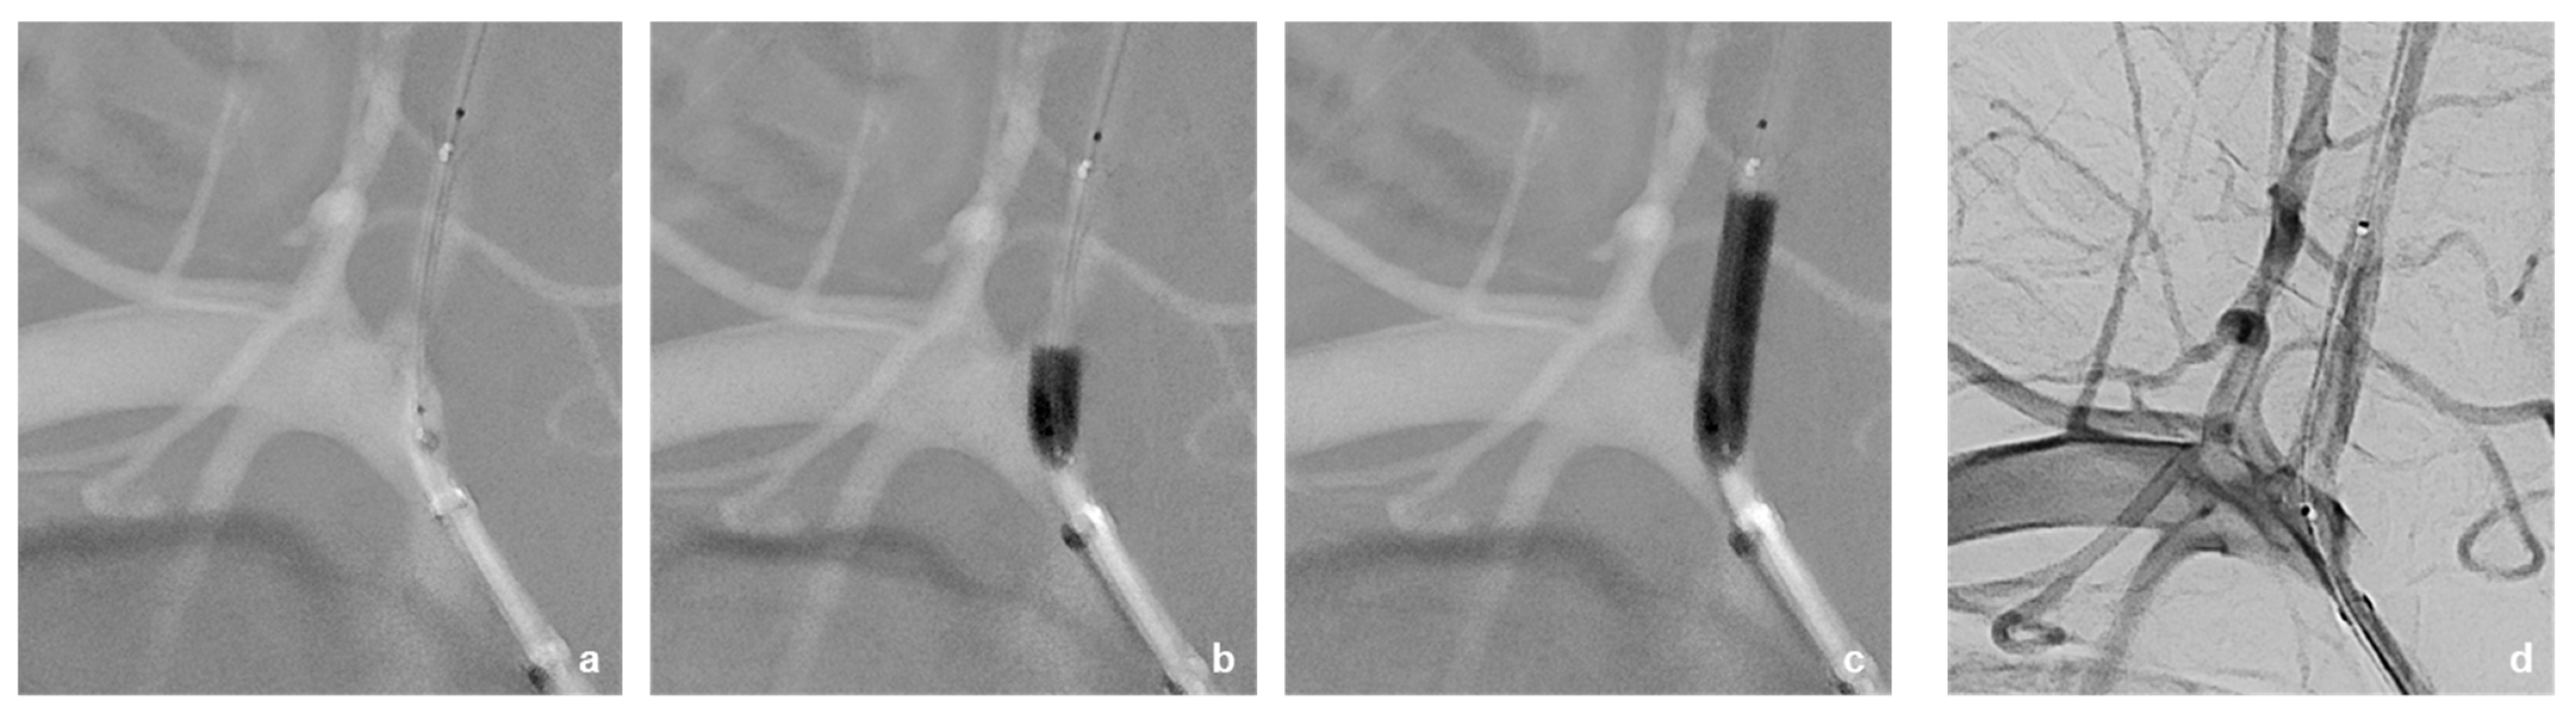

3.2. Neurointerventional Procedure